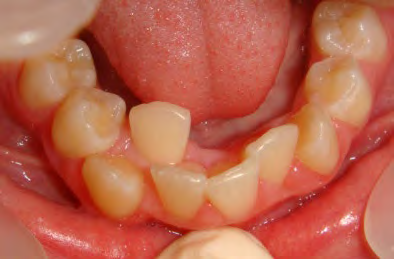

The patient below had severe crowding of both upper canines and the lower right 5. The upper 4’s and 2’s were actually in contact.

Below are cases treated at Vakresmil without extractions within the last three years. The families had been told, “It is simply not possible for your child to be treated without extractions” by orthodontists. Judge for yourself if that was right or wrong.